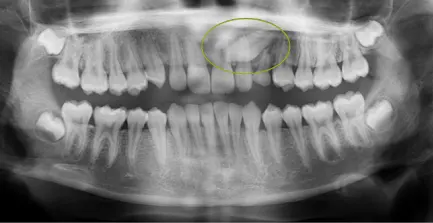

Panorex

A panorex is a two-dimensional x-ray that displays both upper an lower jaws. The x-ray includes a view of all of the teeth, multiple bones of the head and neck, and other critical anatomical structures.